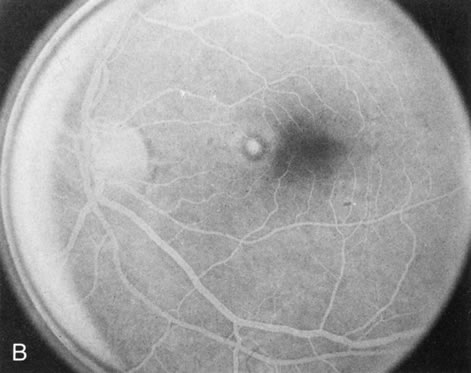

Fundus albipunctatus typically shows multiple, small white dots, which are deep in the retina, regular, and monotonous in their similar size, shape, and color and which involve the entire posterior pole into the equator while sparing the macula (Fig. 3A). These multiple dots are not apparent on FA. There may be a mottling of the background choroidal fluorescence and small areas of irregular transmission hyperfluorescence (especially surrounding the macula), but neither of these findings corresponds to the observed white dots8,9 (Fig. 3B).